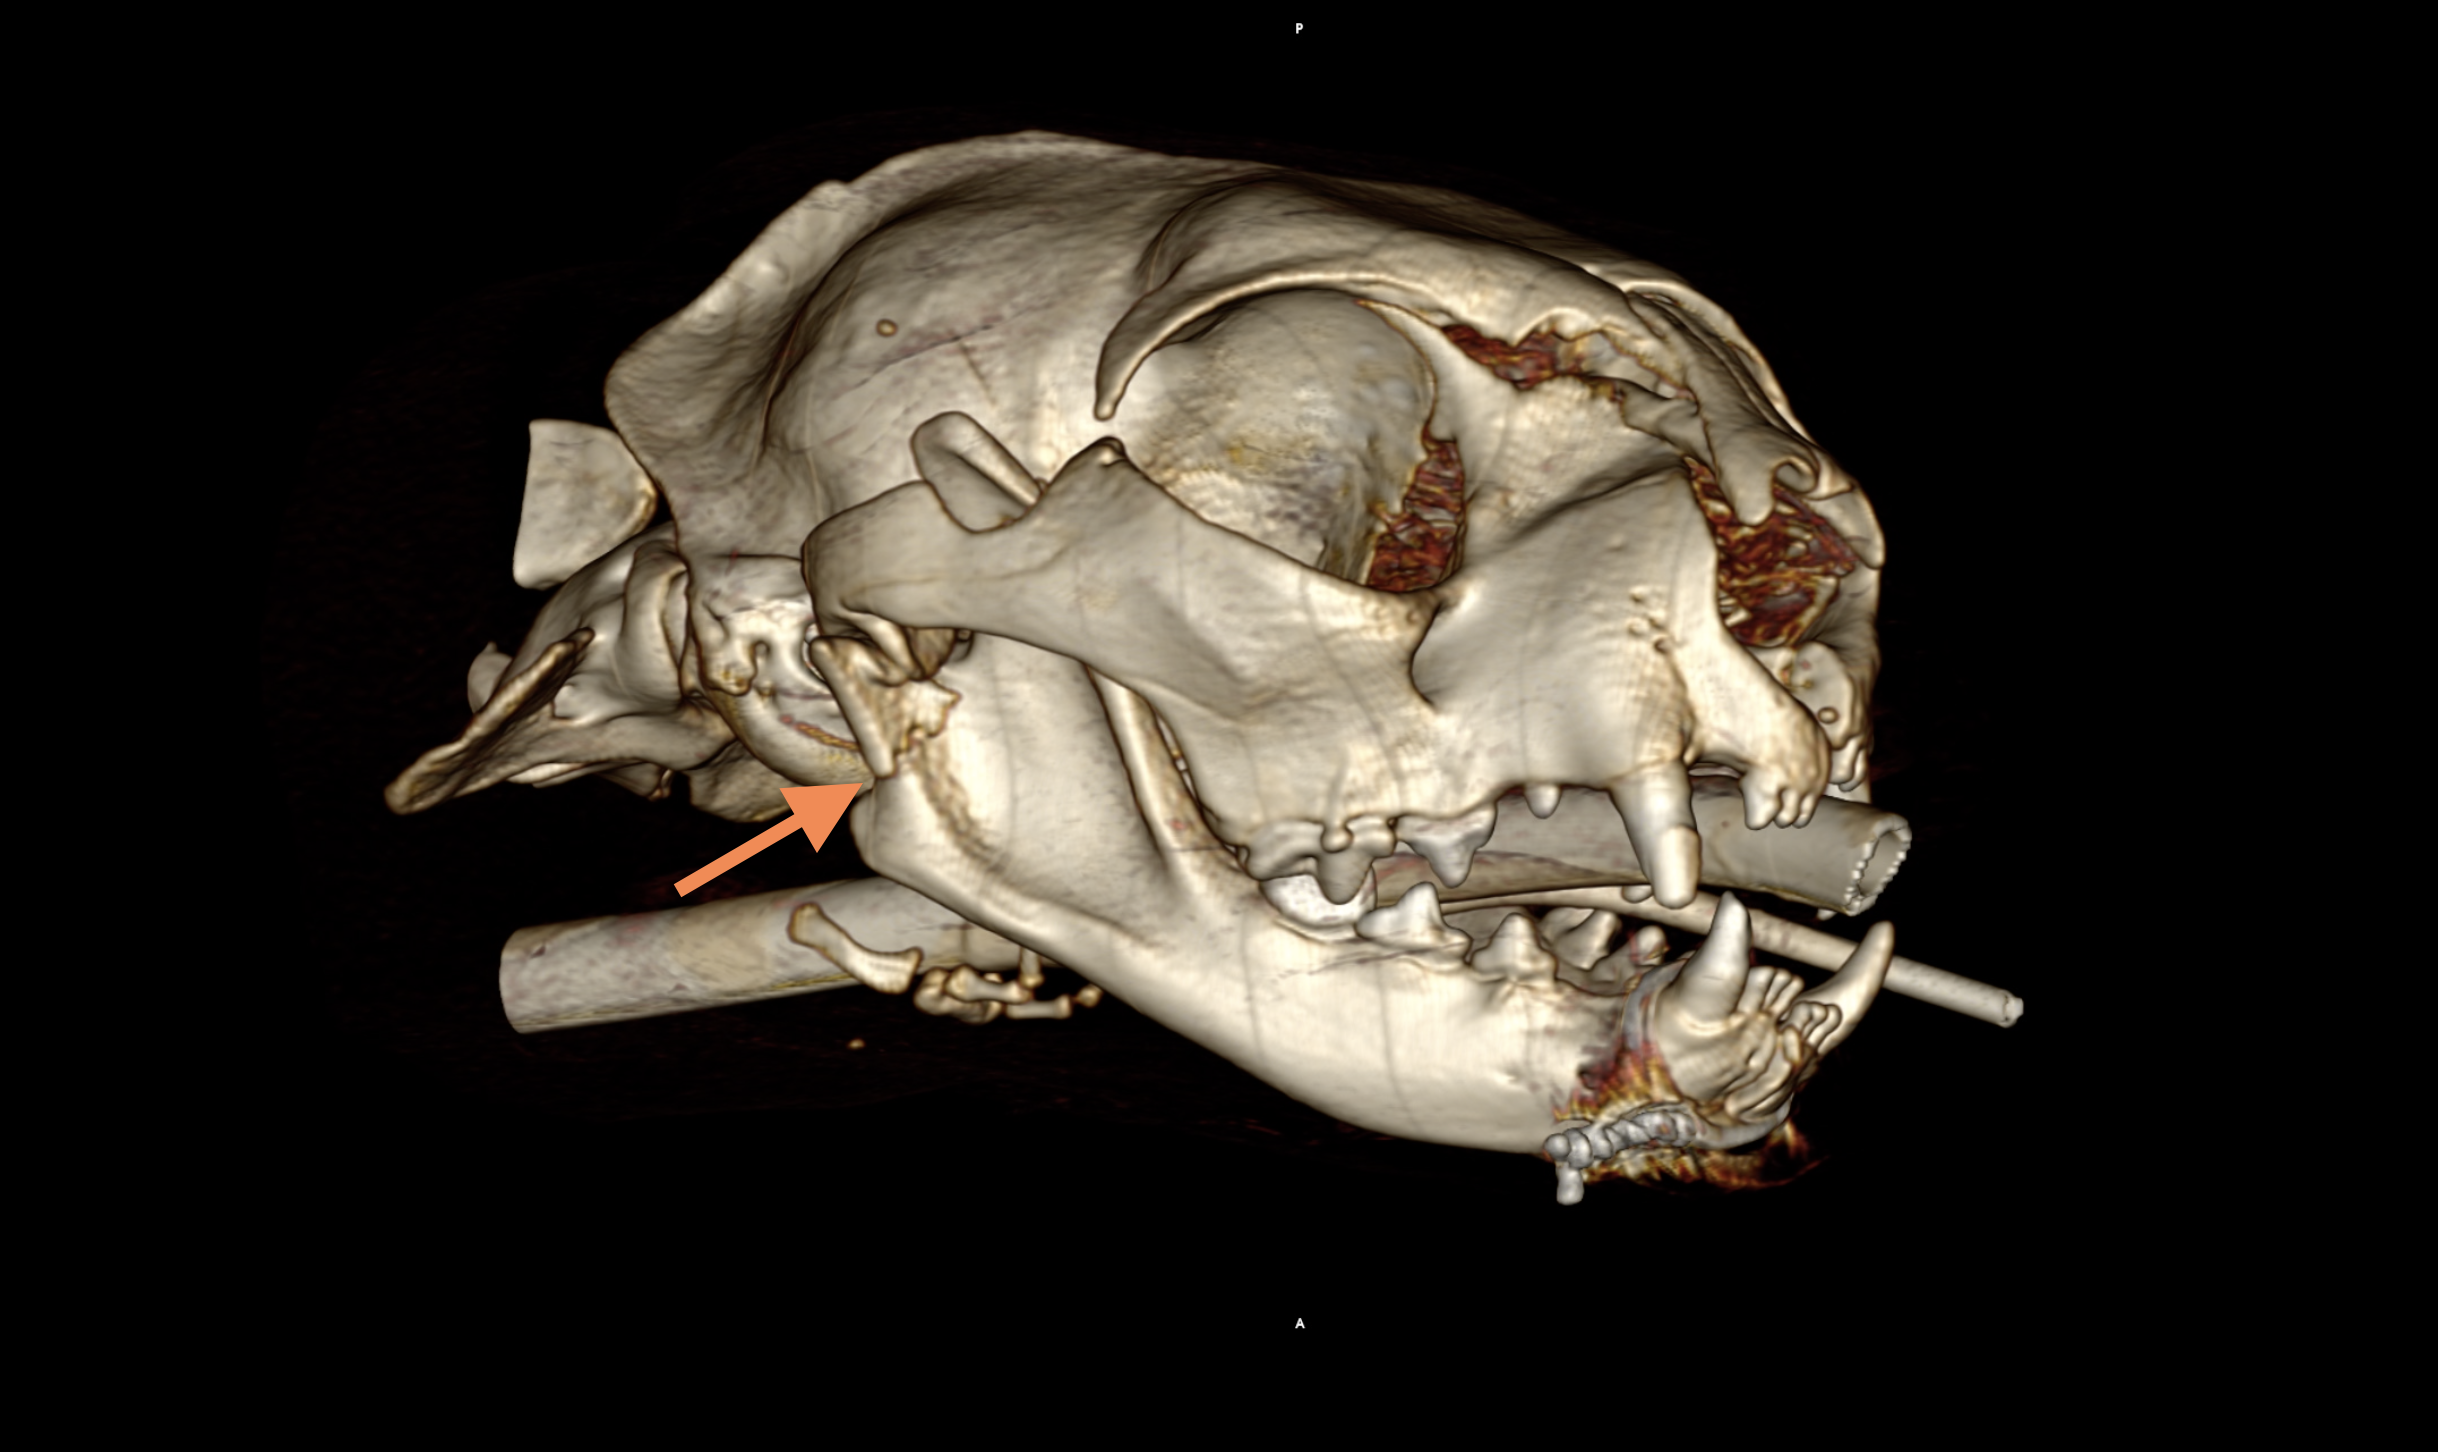

L’animal est anesthésié. L’ouverture de la gueule étant impossible une trachéostomie temporaire a été nécessaire. Pour cela une sonde de trachéostomie est mise en place par trachéotomie ventrale entre le 3eme et le 5eme anneau trachéal. Un abord latéral droit à l’ATM, passant ventralement à l’arc zygomatique, est effectué. Dans un premier temps le pontage osseux entre le bord caudal de la branche montante de la mandibule droite et le processus zygomatique de l’os temporal droit est réséqué à l’aide d’une fraise et d’une pince gouge. Les condyles mandibulaires sont excisés largement en utilisant une scie oscillante, en prenant soin d’éviter l’artère maxillaire, médiale au condyle. Ce protocole opératoire est ensuite répété sur l’ATM gauche.

Voie d’abord chirurgicale. La flèche orange indique le condyle mandibulaire, la jaune indique l’os temporal (orientation : aspect rostral à gauche, aspect caudal à droite).